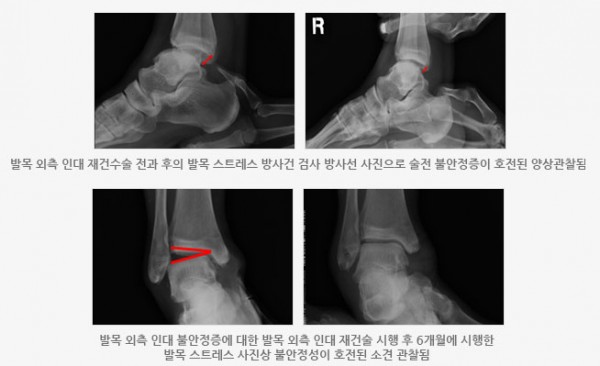

급성 발목 관절 염좌 후에 반복적으로 발목을 삐는 것을 경험하거나 발목의 느슨하고 힘이 잘 안 들어가는 느낌, 계단이나 비탈길 보행시 갑자기 무력해지는 느낌이 드는 경우에 의사의 이학적 검사 및 발목 관절 스트레스 방사선검사, MRI 검사가 필요합니다.

수술적 치료가 필요한 경우는 드물지만 적절한 보존적인 치료에도 불구하고 지속적인 증세가 있고 만성적인 불안정성이 동반될 때 시행한다. 수술 방법은 파열된 인대를 재건하는 것으로 방식에 따라 여러 가지로 나뉘며, 관절 내 손상이 동반되는 경우가 많아서 이를 동시에 치료하기 위해 발목관절 내시경을 시행할 수 있다.